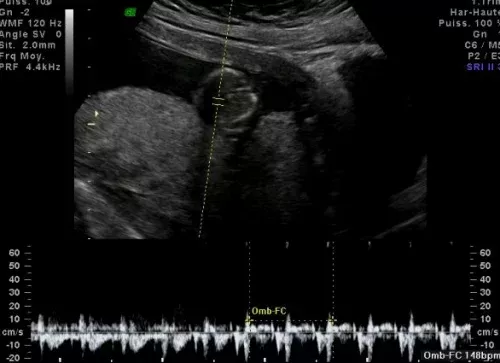

Cette technique dans les conditions d’utilisation médicale est dénuée de risque connu(L’échographie Doppler repose sur le même principe et est parfois utilisée en complément.)

L’échographie du 3ème trimestre

d’apprécier la croissance et le bien être du fœtus ; la position du fœtus et du placenta.

d’étudier la morphologie fœtale, car certaines anomalies ne se révèlent que tardivement dans la grossesse.